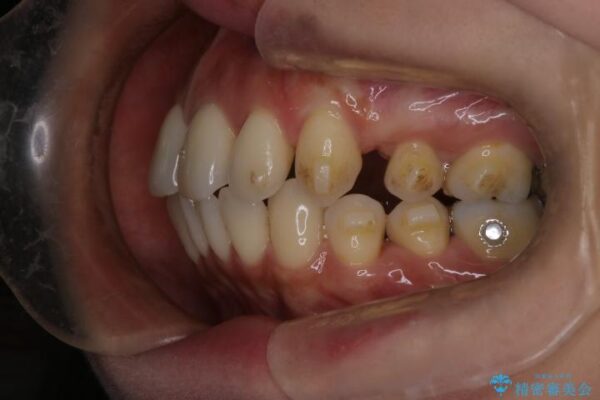

治療途中

• 上顎前歯の突出を軽減 インビザラインによる抜歯矯正 治療途中画像